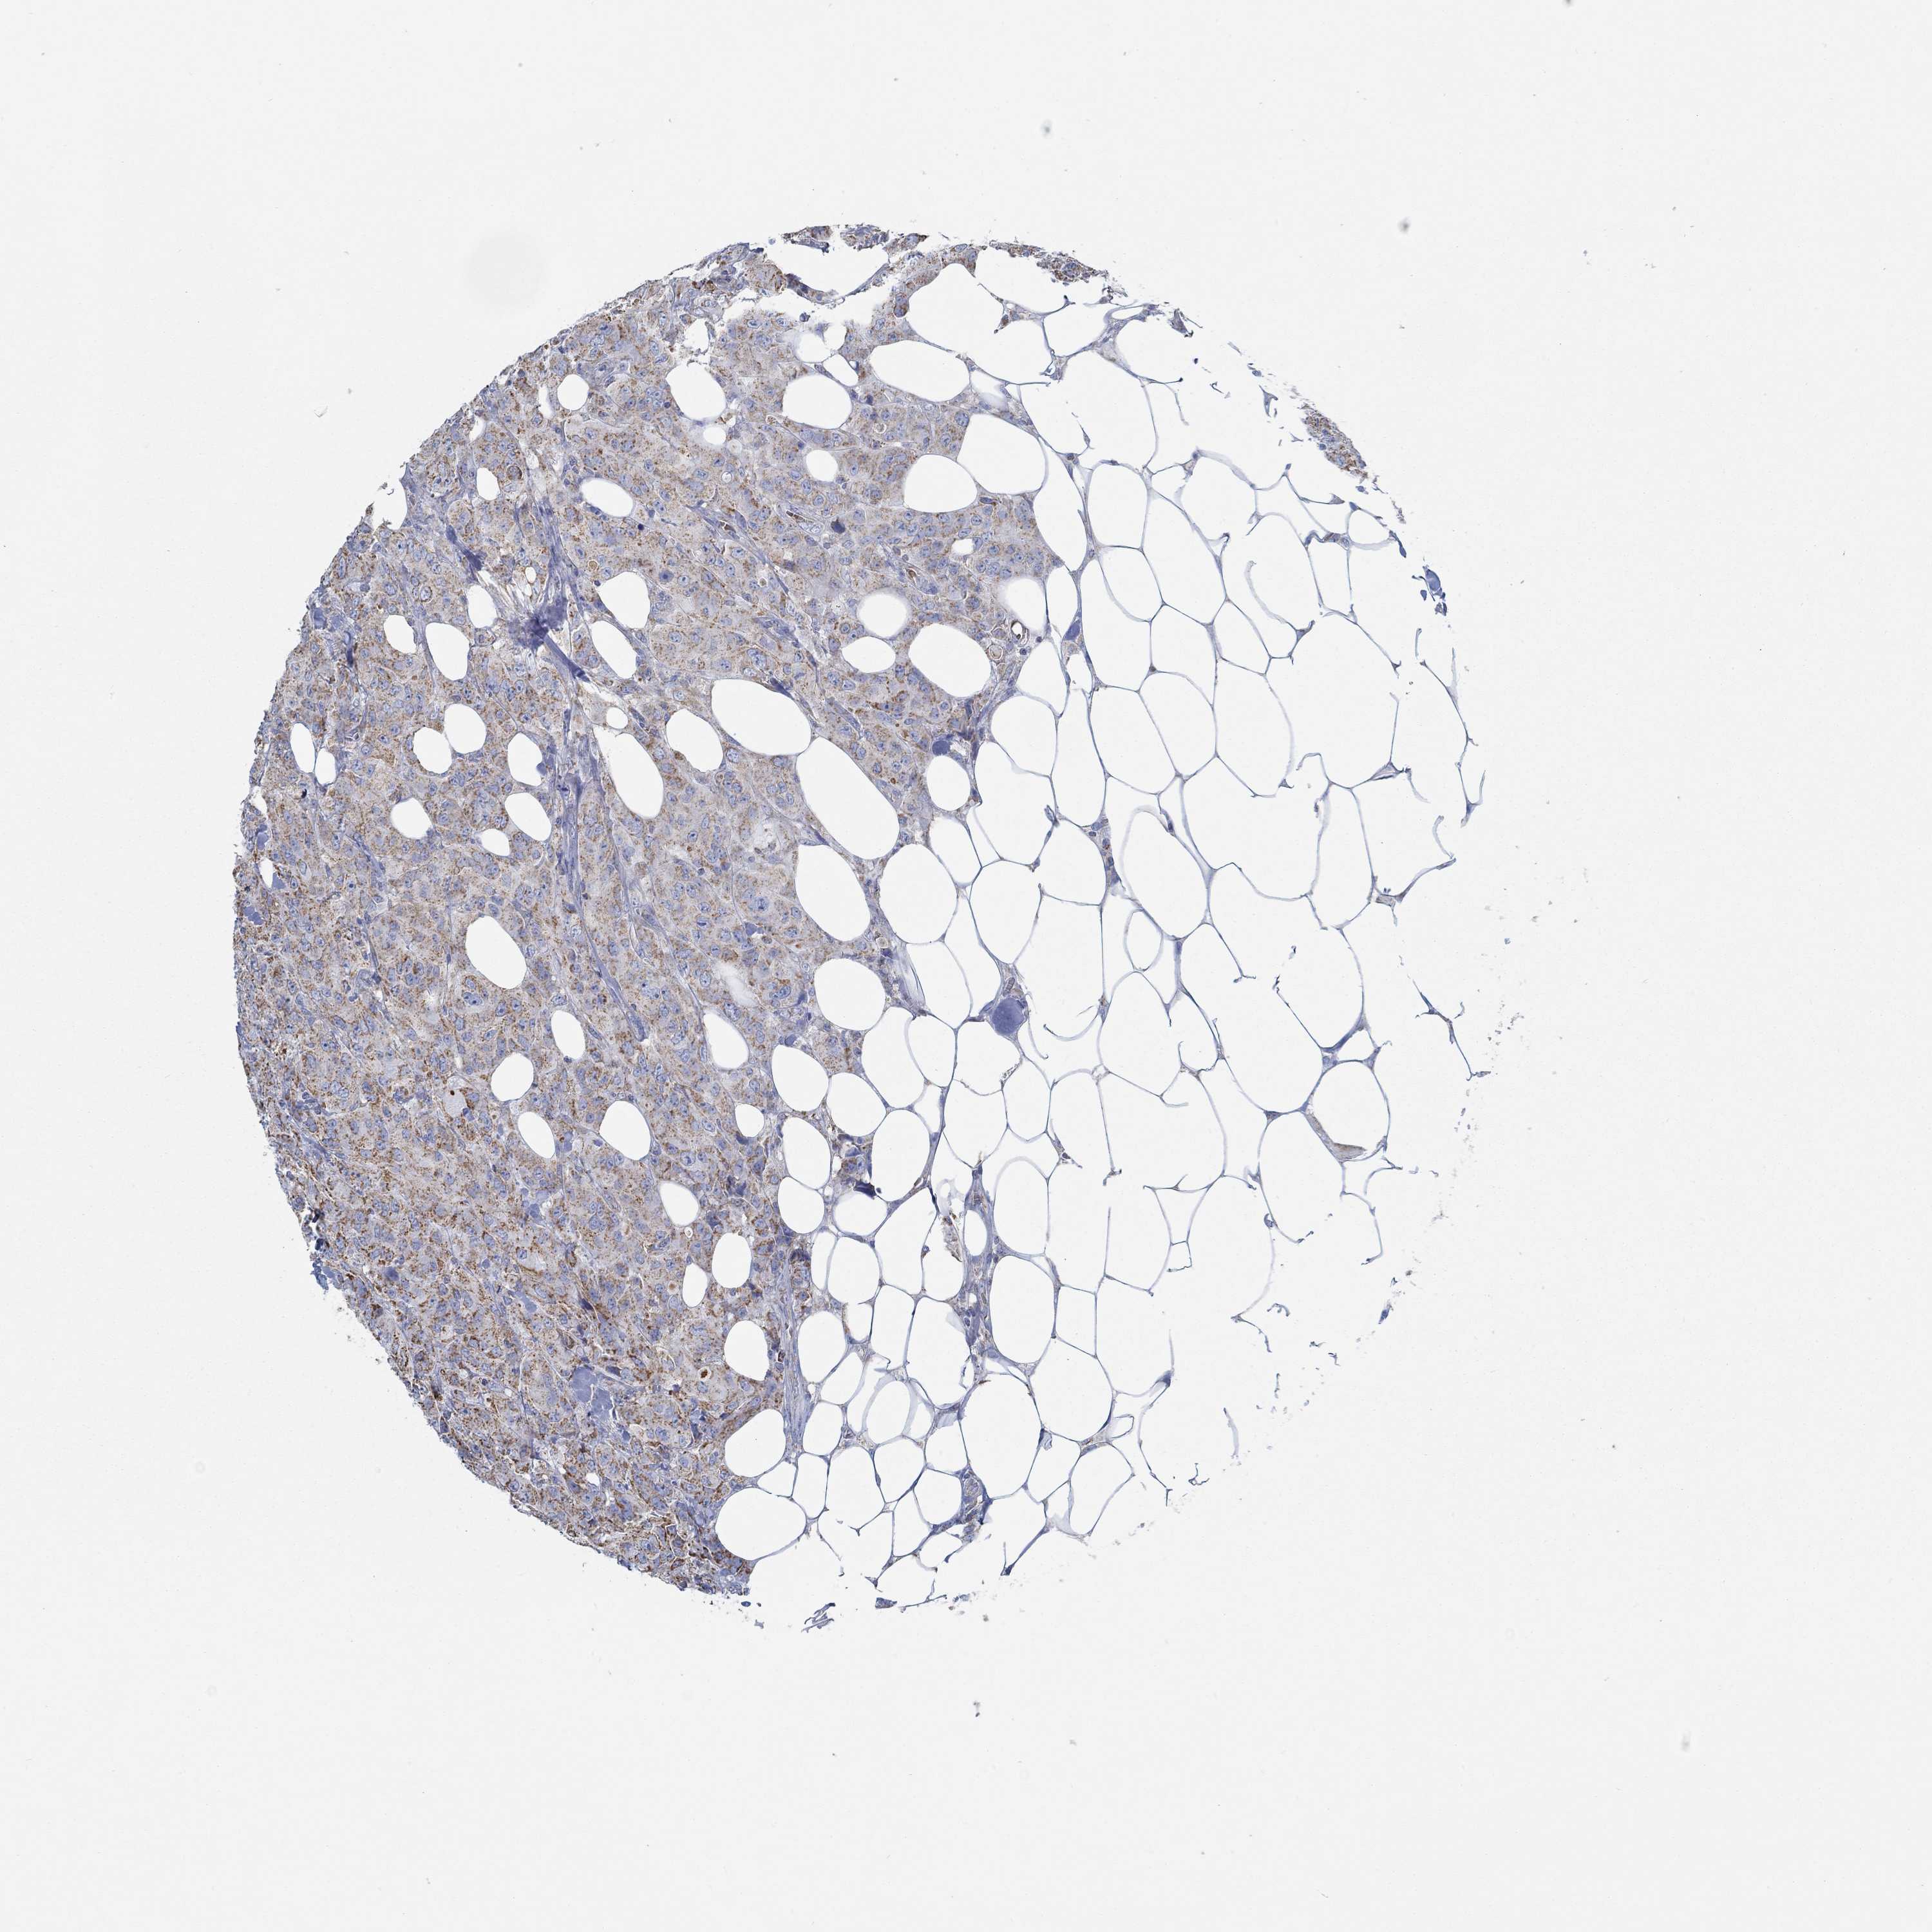

CANCER BREAST CANCER Show tissue menu

BRCA TCGA BRCA VALIDATION PROTEIN EXPRESSION

Breast cancer

Human cancer